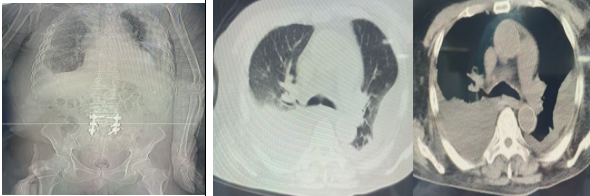

近日,上海龙华医院江西医院(江西省中医院高新院区)重症医学科接诊的首位重症患者——87岁的胡爷爷,经过重症医学科与中医外科的高效协同救治,已于日前顺利出院。这不仅标志着高新院区综合救治能力的正式启用,更是国家区域医疗中心建设在赣鄱大地的一次成功实践。

2025年12月29日,胡爷爷因“乏力纳差、全身水肿、少尿10天”被送入抢救室。当时他血氧饱和度偏低,全身严重水肿,伴有重度贫血、心力衰竭、心房颤动及足趾破溃等多重危重情况。经重症医学科赵文辉主任会诊评估,患者随即被转入ICU进行抢救。

在ICU期间,医疗团队迅速明确了患者水肿的三大主要原因:心源性、营养不良性及下肢静脉回流障碍,并据此制定了包括利尿减轻心脏负荷、输血纠正贫血和低蛋白血症、胸腔穿刺置管引流、抗感染、营养支持及多学科会诊在内的综合治疗方案。经过48小时的积极救治,患者感染指标得到控制,生命体征趋于稳定,全身水肿显著消退,总出入量净负平衡约5800ml(体重约减轻12斤),并成功转入中医外科进行下一阶段康复治疗。

在中医外科,通过中西医结合的序贯治疗,病情得到改善,尤其是全身水肿明显消退,7天引流胸水4200ml,出入量净负平衡约14730ml(相当于体重减轻斤约30斤),出院时胡爷爷开玩笑说:“这次住院的‘减肥’效果真好啊!